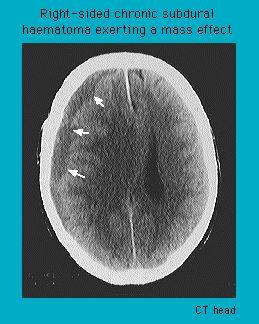

CT scan of a chronic subdural haematoma